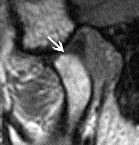

FIGURE 6B - Open position (same patient). Disk remains normally positioned (arrow).